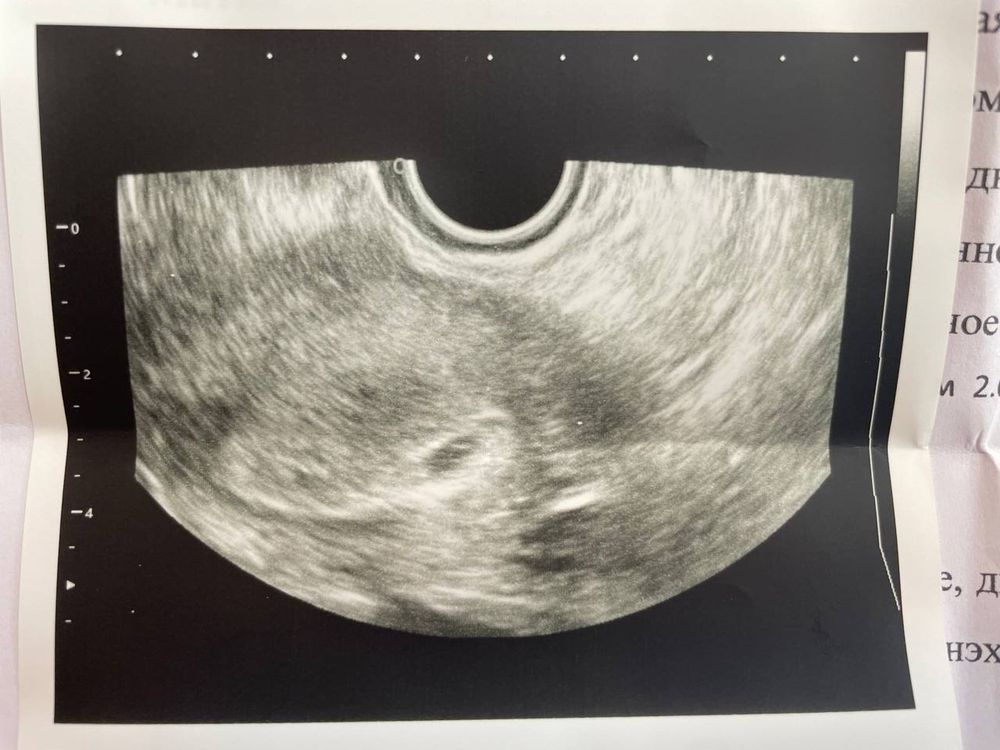

23.11.2023 Подросло мое плодное яйцо (СВД 13х7х9 мм) и визуализируется желточный мешочек 2,6 мм

Срок по узи ставят 4 недели и 3 дня, хотя акушерский 5 нед. и 4 дня.

За 3 дня ПЯ подросло с 4,8 мм (узи было в ПН, 20.11.2023)

Овальная форма плодного яйца-ок.